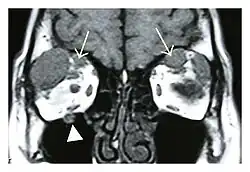

The extent of inflammation that can occur in IgG4-ROD is well demonstrated on magnetic resonance imaging (MRI).

Infraorbital nerve enlargement (IONE) is considered to be a particularly suspicious sign of IgG4-ROD, but seems to occur only when inflammation is in direct contact with the infraorbital canal.[10] IONE is defined as the infraorbital nerve diameter being greater than the optic nerve diameter in the coronal plane.